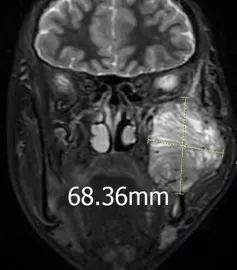

来自偏远地区的18岁的藏族小伙才让多杰(化名),近一年来因右侧面部逐渐肿胀增大,且伴有疼痛不适,在当地医院就诊,检查发现他的右侧面部有一约7cmx9cm的肿物,活检穿刺后病理结果提示为“梭形细胞瘤”,结合免疫组化染色结果,多考虑孤立性纤维性肿瘤(孤立性纤维瘤是一种罕见的低度恶性肿瘤)。经朋友推荐,才让多杰在哥哥的陪同下来到了联勤保障部队第940医院颌面外科就诊。在完善相关检查后,才让多杰的病情得到了进一步确诊,进入了紧张而有序的手术准备阶段。

由于才让多杰的肿瘤主要在颅底,已经侵犯到部分下颌骨、面神经和周围的肌肉组织,为达到较好的手术效果,颌面外科马东洋主任组织全科人员对才让多杰的病情进行分析讨论,认为患者肿瘤位置特殊,周围重要解剖结构多,如何最大程度规避风险,降低手术并发症,对肿瘤扩大切除术后造成的下颌骨部分缺失,使用何种方法进行同期修复,是本次手术中需要解决的重要问题。经过讨论,专家团队决定采用数字化3D打印、CT导航和虚拟手术技术对才让多杰的肿瘤位置、大小及周围重要解剖结构进行详细评估,同时对切除部分下颌骨后使用带血管蒂腓骨移植修复方案进行模拟,以达到精准的修复效果。